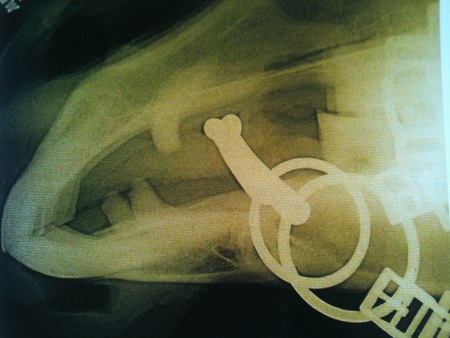

Správne zvolené a používané zubadlo je aj správne umiestnené. Každé nepohodlie koňa, spôsobené zubadlom, vychádza z jeho vulgárneho alebo nesprávneho používania. Takéto zubadlo koňa tlačí a môže sa mu dokonca dotýkať zubov, čo je nemožné, pokiaľ jazdec nepôsobí rukou výrazne dozadu alebo pokiaľ nemá kôň hlavu v nesprávnej pozícii (tzn. za kolmicou). Na obrázku je kôň na normálnom kontakte. Pokiaľ jazdíte správne a nenutíte koňa nosiť hlavu za kolmicou, zubadlo sa zubov nebude dotýkať a predídete mnohým problémom.

Zdroj obr. 1: The effects of the bit